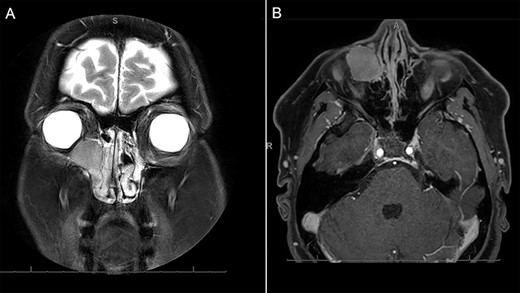

A 46-year-old woman presented with a 5-month history of a gradually enlarging, non-painful swelling her right medial canthus. She reported mild right-sided nasal obstruction that predated the lesion but denied any history of epiphora, visual disturbance, epistaxis or facial pain/paraesthesia. On further questioning, she did report some discomfort with inferior gaze without diplopia. Her medical history was notable only for asthma. Examination revealed a palpable cystic lesion of the right medial canthus and infraorbital tissue extending over her right nasal bridge. There was no hyoglobus. Severe right septal deformity prevented visualization of the right inferior meatus, but the lateral nasal wall did not demonstrate deformity. Magnetic resonance imaging (MRI) demonstrated a 23 × 18.8 × 23.7 mm well-circumscribed cystic mass centred on the right lacrimal sac extending into the middle and inferior meatus. The lesion was isointense to muscle on T1 and markedly hyperintense on T2. It enhanced homogenously with contrast (Fig. 1). Expansile erosion of the right medial orbital wall, floor, anterior maxillary sinus and lateral nasal bone was noted with displacement of the medial rectus muscle inferolaterally (Fig. 2).

MRI demonstrating (A) coronal T2 demonstrating a homogenous, markedly hyperintense lesion of the right medial orbit, extending into the lacrimal duct. The contrast enhanced axial T1-weighted imaging demonstrates homogenous enhancement of the lesion with contrast.